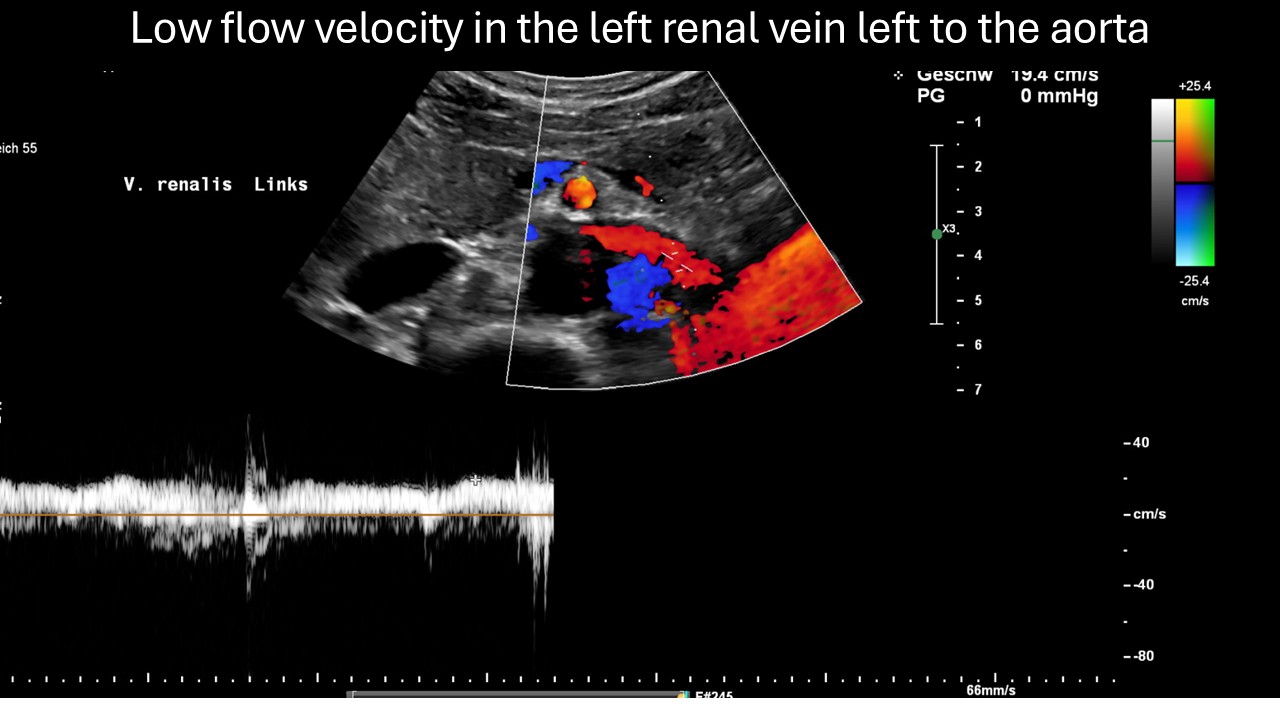

Colour duplex sonography revealed a nutcracker constellation of the left renal vein

and a strong venous connection from the spine to the left renal vein, known as a tronc réno-rachidien. This vessel serves to equalise pressure between the renal vein and the epidural plexus. The fact that blood flow to the left kidney was significantly lower than to the right kidney, even with normal head posture, indicates the inability of the collateral circulation to adequately drain congested blood from the left renal vein.